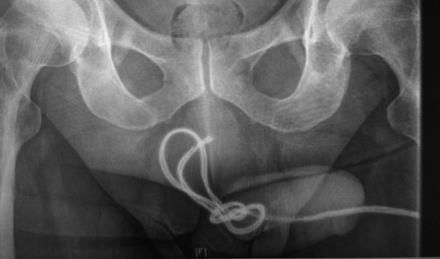

Die Urethra wird am häufigsten bei autoerotischen Aktivitäten verletzt. Betroffene führen unterschiedliche Fremdkörper in die Harnröhre ein, um die transurethralen Sexualrezeptoren zu stimulieren. Dabei kommt es entweder zur direkten Perforation der Harnröhre, meist im bulbären Bereich, zur Blasenperforation oder auch zu spezifischen Komplikationen, wenn sich z. B. ein Kabel verknotet oder ein Gegenstand zerbricht. Meistens gelingt eine minimalinvasive endourologische Lösung des Problems. Mitunter muss aber auch operativ interveniert werden. In unserer Klinik mussten wir zum Beispiel einmal ein zerbrochenes Reagenzglas in mehreren Teilen aus der Urethra bergen, wobei die Glasteile sehr schwer mit der Fasszange zu greifen waren. In einem anderen Fall mussten wir einen Bleistift, der transurethral eingeführt die Harnblase perforiert hatte, mit einem Holmium-YAG-Laser zerlegen, um ihn herauszuholen.

Die Urethra wird am häufigsten bei autoerotischen Aktivitäten verletzt. Betroffene führen unterschiedliche Fremdkörper in die Harnröhre ein, um die transurethralen Sexualrezeptoren zu stimulieren. Dabei kommt es entweder zur direkten Perforation der Harnröhre, meist im bulbären Bereich, zur Blasenperforation oder auch zu spezifischen Komplikationen, wenn sich z. B. ein Kabel verknotet (Abb. 1) oder ein Gegenstand zerbricht.